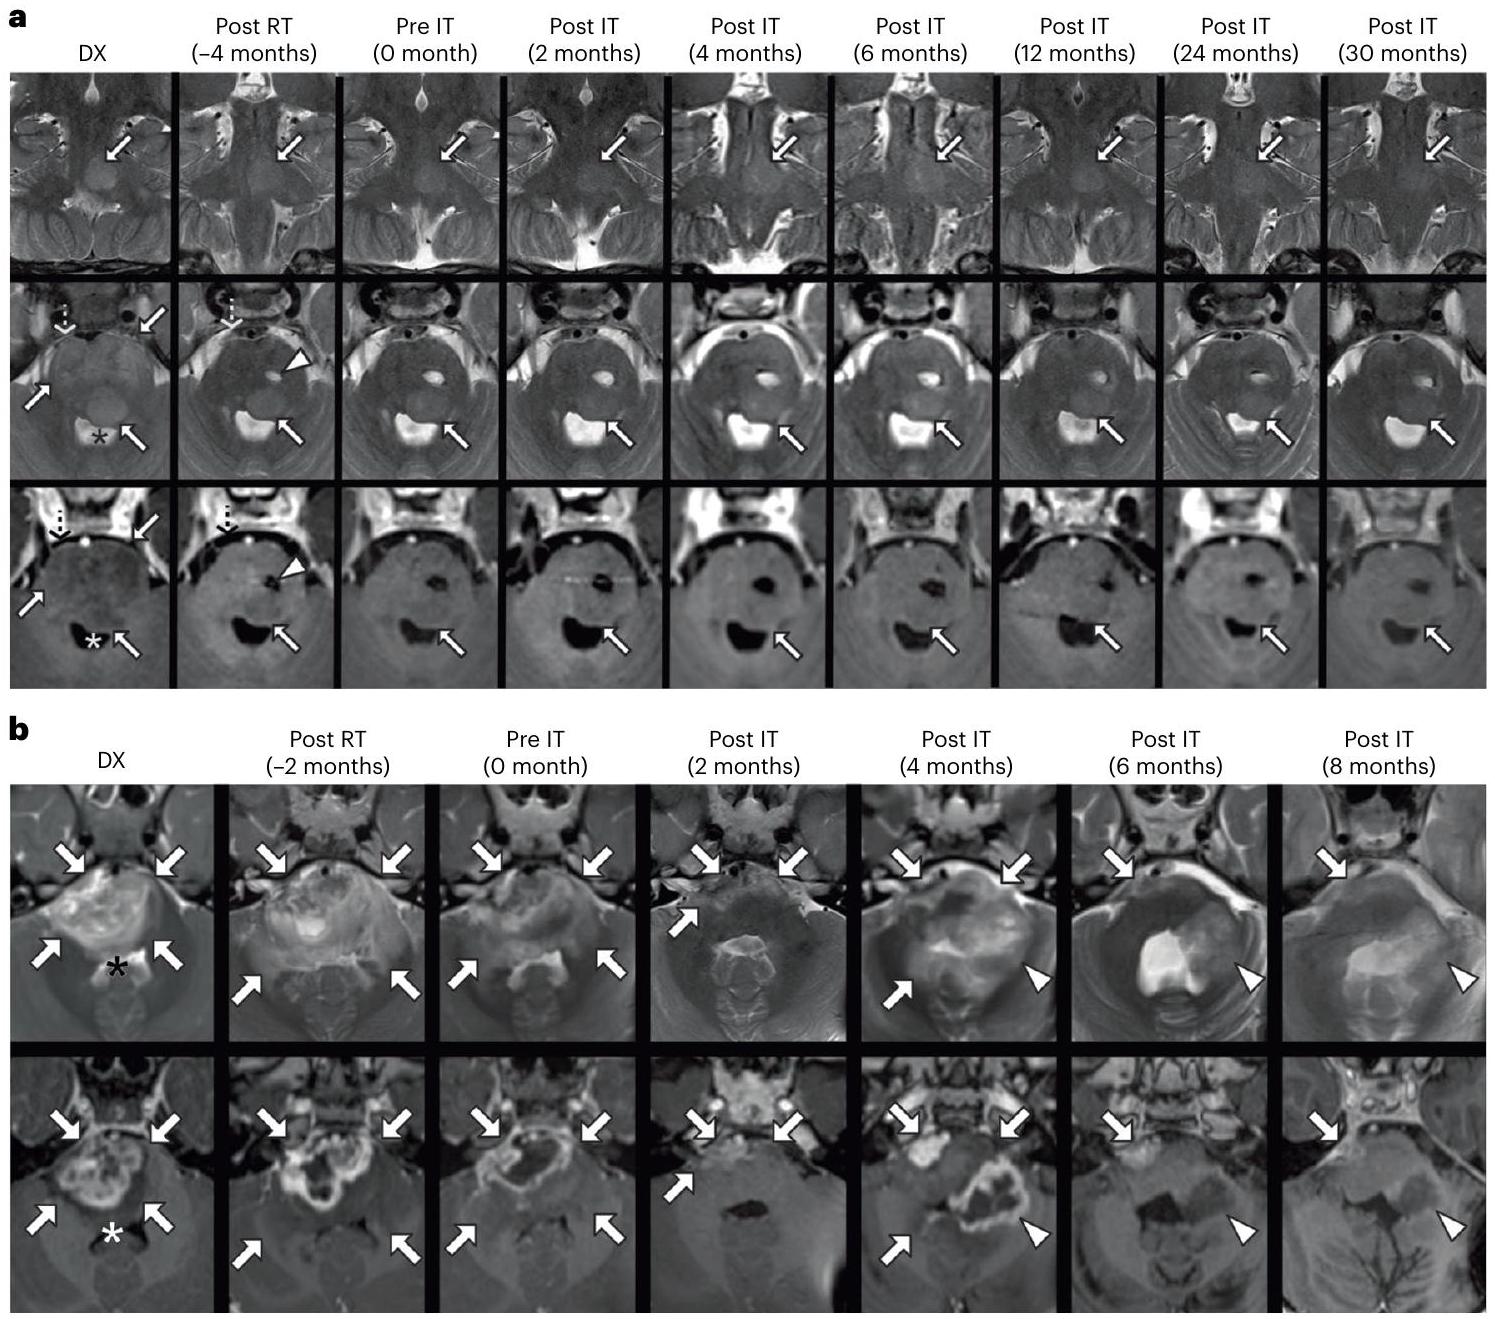

The discussion section of the BrainChild-03 Arm C trial presents findings from a phase 1 study investigating the safety and efficacy of intracerebroventricular (ICV) administration of B7-H3 CAR T cells in children and young adults with diffuse intrinsic pontine glioma (DIPG). Among the 21 patients treated, the most common adverse events (AEs) included headache and nausea, with most AEs classified as grade 1 or 2. Notably, the only dose-limiting toxicity (DLT) was an intratumoral hemorrhage in a patient with progressive disease. The trial demonstrated the feasibility of administering up to $10^7$ CAR T cells per dose, with a cumulative total of $3 \times 10^9$ CAR T cells delivered to one patient.

Clinical outcomes indicated a median survival of 19.8 months from diagnosis for treated patients, surpassing historical survival rates. The study also highlighted the detection of CAR T cells in cerebrospinal fluid (CSF) and significant elevations in cytokines associated with immune activation post-infusion, suggesting locoregional CAR T cell activity. While the results are promising, the authors caution that the study’s phase 1 nature limits definitive conclusions regarding efficacy. Future phase 2 trials are planned to further evaluate the therapeutic potential of ICV B7-H3 CAR T cells, alongside ongoing preclinical efforts to enhance CAR T cell functionality and explore combinatorial treatment strategies.